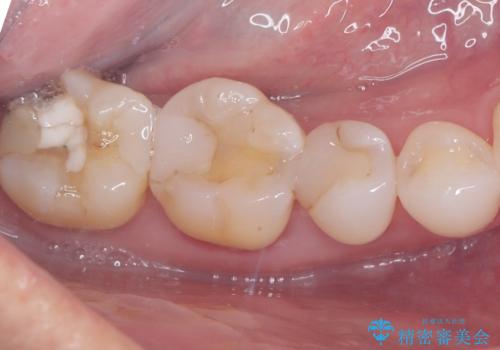

右下の奥歯にあった古い金属製のクラウンは、見た目の問題や歯ぐきの変色、さらには歯との境目に汚れが溜まりやすいなどの課題がありました。今回は審美的に優れ、生体親和性が高いセラミック素材を使用してクラウンを製作。色調は患者様の天然歯に合わせて調整を行い、自然で違和感のない仕上がりを目指しました。さらに精密な型取りと高度な技工技術を駆使することで、適合精度が非常に高いクラウンを提供しています。治療後は、見た目の美しさと噛み合わせの快適さが向上し、患者様には大変満足いただけました。